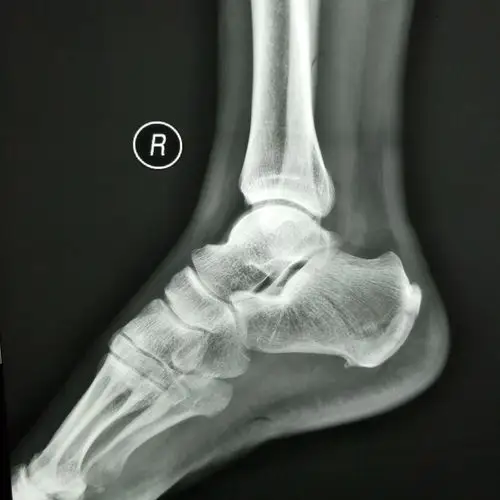

右跟骨侧位片(长度,高度尚可,盖世角120度左右,贝氏角存在)